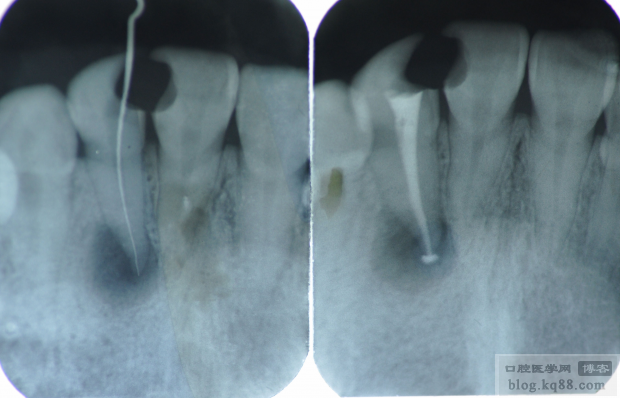

22根尖區(qū)陰影,但是該牙未見明顯不適,所以行一次性根管治療(插針片和根充片如下)

根充完成后取模